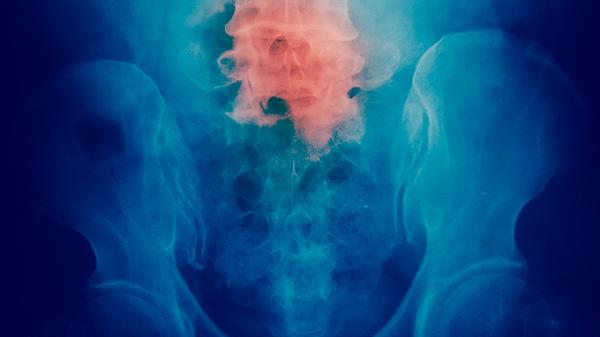

CEA显著升高需警惕恶性肿瘤可能。非小细胞肺癌患者CEA阳性率较高,当肿瘤侵犯支气管黏膜或发生远处转移时,CEA数值可能急剧上升,需结合胸部CT和病理活检明确诊断。结直肠癌患者随着肿瘤体积增大和分期进展,CEA释放入血增多,同时可能出现便血、肠梗阻等症状。胃癌晚期伴腹膜转移时CEA水平往往明显增高,胃镜取组织病理检查是确诊依据。